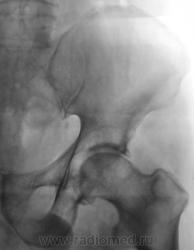

В принципе, болеть есть от чего. Однако, у меня на подозрении очаги разрежения структуры в головке левой бедренной кости и в теле правой подвздошной кости над вертлужной впадиной. Очаги весьма четкие, круглые - дообследуйте на предмет миеломной болезни.

Справа на фоне лонной и седалищной костей по-видимому тени кишки - грыжа?

Бластического варианта НЕТ. Очаги просветления, в данном случае -затемнения газ в к-ке. ДОА пр.т/б сустава 4 , левого - 2 степени, артрозные изм-я в сакроилеальных сочленениях, выраженней в левом

Правая половина таза меньше за счёт проекционного искажения?

Да, положение вынужденное.